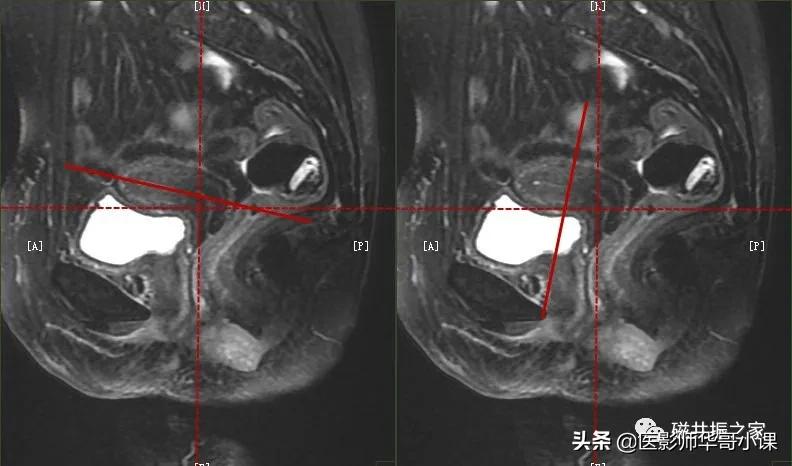

在冠状位和矢状位上定位,在矢状位上找到显示子宫全景最好的层面,如需了解宫颈病变,使定位线垂直于宫颈管长轴(图A),如需了解子宫内膜病变,使定位线垂直于子宫内膜长轴(图B)。在冠状位调整角度使两侧对称扫描,扫描范围上至子宫上缘下至耻骨联合,需包括整个病变范围,如观察转移性病变需加大扫描范围。

在横轴位和矢状位上定位,在矢状位上找到显示子宫全长最好的层面,如需了解宫颈病变,使定位线平行于宫颈管长轴(图A),如需了解子宫内膜病变,使定位线平行于子宫内膜长轴。在横轴位上找到显示子宫最大的层面,使定位线平行于当前子宫内膜长轴,扫描范围包括整个子宫及两侧附件,需包括整个病变范围。